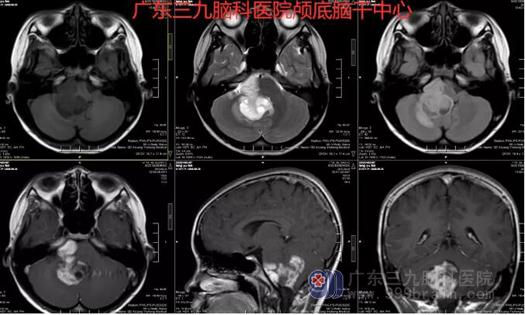

图2:术前MR示四脑室右侧侧孔-桥小脑角区不规则团块状占位性病变,呈不匀长T1长T2异常信号影,FLAIR序列呈高信号间杂多发斑点、斑片状低信号,增强后呈明显不均匀强化;病变边界清,大小约48mm*38mm*35mm,累及四脑室室壁,四脑室下部明显受压变窄;邻近脑组织受压移位、变形,右侧小脑半球并示条片状稍长T1长T2、FLAIR序列高信号水肿影。